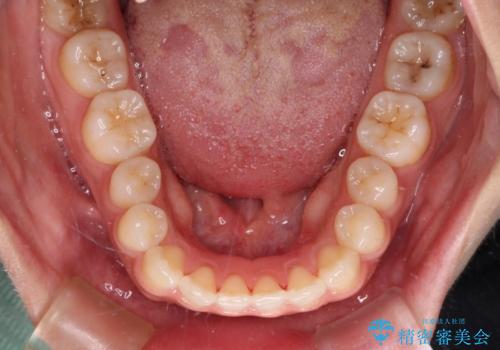

- 上顎前歯の叢生を気にして来院された患者様です。

下顎前歯や上下奥歯の咬み合わせには殆ど問題がないため、上顎前歯のみを矯正する治療を提案しました。

ワイヤー装置でもインビザラインでも可能でしたが、前歯のみをきれいに排列するのであればインビザラインの方が仕上がりが良いので、インビザライン・ライトにて治療を行うこととしました。